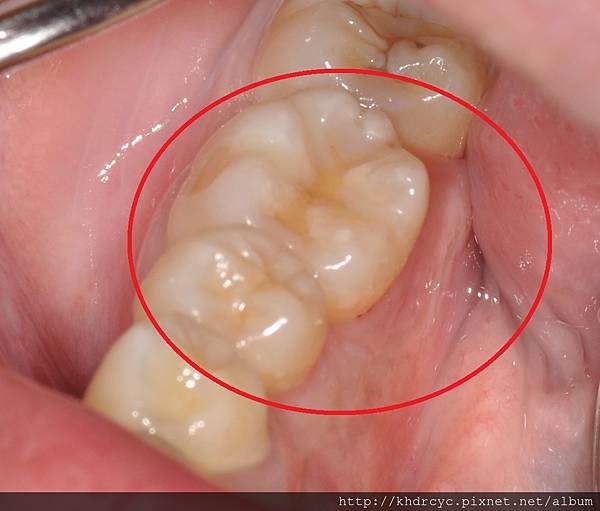

[牙肉腫很大 痛是還好 只是有點擔心]

這種牙肉發炎後腫起來

是因為發炎的部位積膿

在牙齒與牙肉中間排不出來

最後過多的膿把牙肉都撐開變成膿包

消腫之後常可以明顯看到殘留的牙結石